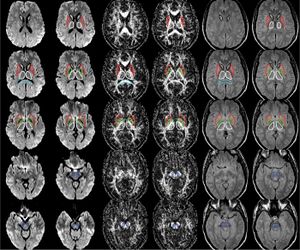

Publication: PLoS One. 2015 Dec 29;10(12):e0145493. PMID: 26713760 | PDF Authors: Esterhammer R, Seppi K, Reiter E, Pinter B, Mueller C, Kremser C, Zitzelsberger T, Nocker M, Scherfler C, Poewe W, Schocke M. Institution: Department of Radiology, University Hospital, Innsbruck Medical University, Innsbruck, Austria. Background/Purpose: The purpose of the present study was to evaluate the potential of multimodal MR imaging including mean diffusivity (MD), fractional anisotropy (FA), relaxation rates R2 and R2* to detect disease specific alterations in Parkinson's Disease (PD). We enrolled 82 PD patients (PD-all) with varying disease durations (≤5 years: PD≤5, n = 43; >5 years: PD>5, n = 39) and 38 matched healthy controls (HC), receiving diffusion tensor imaging as well as R2 and R2* relaxometry calculated from multi-echo T2*-weighted and dual-echo TSE imaging, respectively. ROIs were drawn to delineate caudate nucleus (CN), putamen (PU), globus pallidus (GP) and substantia nigra (SN) on the co-registered maps. The SN was divided in 3 descending levels (SL 1-3). The most significant parameters were used for a flexible discrimination analysis (FDA) in a training collective consisting of 25 randomized subjects from each group in order to predict the classification of remaining subjects. PD-all showed significant increases in MD, R2 and R2* within SN and its subregions as well as in MD and R2* within different basal ganglia regions. Compared to the HC group, the PD≤5 and the PD>5 group showed significant MD increases within the SN and its lower two subregions, while the PD≤5 group exhibited significant increases in R2 and R2* within SN and its subregions, and tended to elevation within the basal ganglia. The PD>5 group had significantly increased MD in PU and GP, whereas the PD≤5 group presented normal MD within the basal ganglia. FDA achieved right classification in 84% of study participants. Micro-structural damage affects primarily the SN of PD patients and in later disease stages the basal ganglia. Iron contents of PU, GP and SN are increased at early disease stages of PD. Funding:

The regions-of-interest (ROIs) were manually drawn by an experienced radiologist by using the b 1000 images, averaged for all measured directions, the FA maps and the proton-density weighted images. For that purpose, the maps of ADC, FA, R2 and R2* as well as the proton-density weighted images were first co-registered. The ROIs were segmented by syncing the b 1000 images, averaged for all measured directions, the FA maps and the proton-density weighted images in ImageJ. The ROIs were stored in the ROI manager and transferred to the co-registered maps. The segmented brain regions were highlighted in different colors: CN—black; PU—red; GP—green; TH—white; SN—blue; CC—cyan. The diffusion-weighted images, the R2 and R2*-weighted maps were transferred to the 3D Slicer software in order to co-register the R2 and the R2* maps as well as the MD and the FA maps |